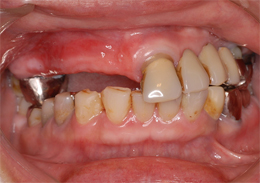

- 主訴

- 歯周病で歯がグラグラするので噛めない

- 治療内容

- 上顎に残存していた歯を抜歯。歯肉の治癒後にフラップレス手術にてインプラント埋入を行い、その場で準備してあった上顎上部構造を仮歯として、ねじ固定式で装着